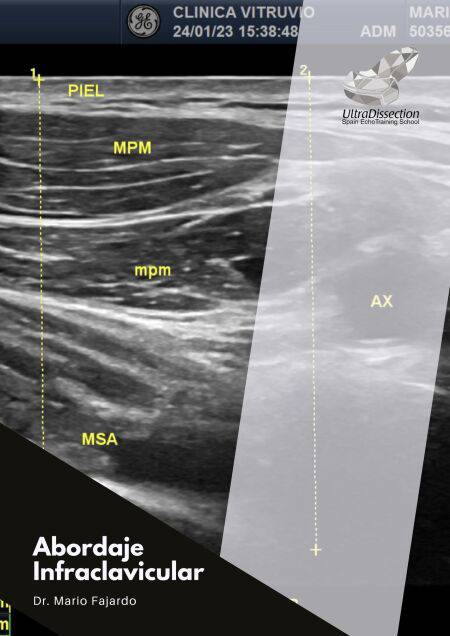

Desde las primeras páginas, el lector es llevado de la mano a través de fundamentos anatómicos, indicaciones precisas y mitos comunes sobre el procedimiento, como el temido riesgo de neumotórax. Con apoyo de ilustraciones clínicas y ecográficas (como se muestra en la imagen de la página 7, que compara la distancia piel-pleura), Fajardo construye un argumento sólido que invita al lector a perderle el miedo a esta técnica.

El texto no sólo describe la técnica clásica, sino que ofrece variantes como el abordaje subclavicular o clavipectoral, útiles en escenarios clínicos complejos como pacientes con collarín cervical o movilidad restringida del brazo (ver imagen en página 20). La metodología de ejecución está explicada paso a paso, destacando detalles prácticos como la posición ideal del paciente, orientación de la sonda, trayectorias de la aguja y uso de neuroestimulación.